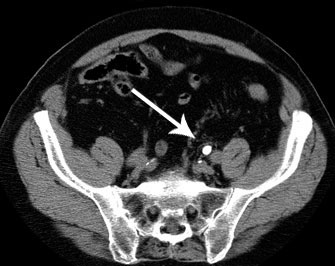

Tamsulosina en el cólico ureteral

La revisión muestra que favorece la eliminación de cálculos de entre 5 y 10 mm de diámetro. Annals of Emergency Medicine, 8 de septiembre de 2016